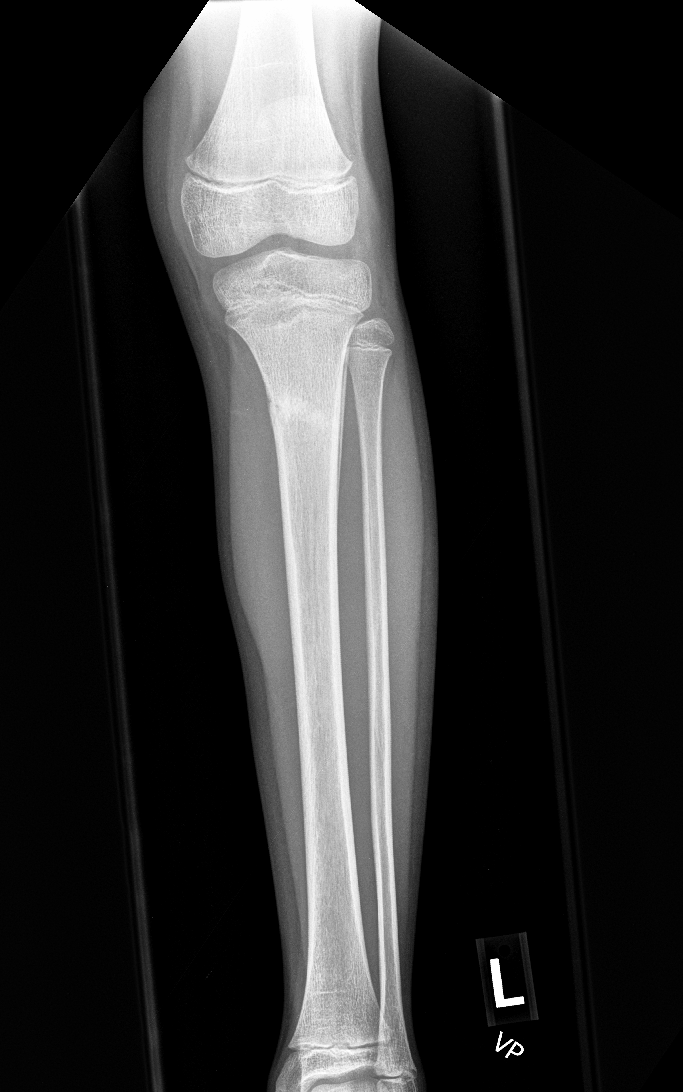

Info Images Findings Impression Reco/Acuity Case Images View Images / Launch Visage Case Notes History 2-month-old presents with decreased right arm movement, increased fussiness, and increased sleepiness for 2 days. Suspected non-accidental trauma. Exam Skeletal survey Prior Study none Dicom View Reference Material

Section 1 Submit Findings CB1550 Findings Skeletal Survey - Technique Check Skull AP/Lat Yes No Cervical and Thoracolumbar spine Yes No Chest X-Ray Yes No Ribs – Left/Right Oblique Yes No Abdominal X-Ray Yes No Pelvis with both hips Yes No Bilateral Humerus, Forearm, Hand Yes No Bilateral Femur, Tibia/fibula, feet Yes No Any additional lateral views of the extremities Yes No The exam is over or under penetrated. Yes No The exam may or may not be limited by overlying structures or soft tissues, body habitus, patient positioning, support devices, or motion. Yes No The area of concern is indicated by the patient, technologist, or care provider. Yes No The area of concern is included on the exam. Yes No Soft Tissues There is soft tissue swelling, indistinctness of fat/muscle planes, gas, or laceration in the area of clinical concern. Yes No There is an effusion, fat pad displacement, or fat fluid level. Yes No There is a radiodense or lucent foreign body. Yes No There are other densities, calcifications, post-surgical changes, or support devices in the soft tissues. Yes No Any support lines/tubes. Yes No Bone There is a break or interruption of the continuity of the cortical or cancellous bone. Yes No There is overriding of the trabeculae with apparent sclerosis. Yes No There is displacement of a fracture fragment. Yes No There is bowing of the bone in addition to the fracture at the apex of the bowed bone concerning for the greenstick. Yes No There is a spiral fracture of the leg concerning for toddler’s fracture. Yes No There is abnormal angulation or bulging of the cortical surface relative to the normal cortex which could be from a buckle or torus fracture. Yes No There is a displaced fragment which may be from avulsion by a tendon, ligament, or joint capsule or from a comminuted or other fracture. Yes No The stress trabeculae or other trabeculae of the cancellous bone are interrupted or otherwise abnormal. Yes No There is subperiosteal or endosteal reaction which could indicate a healing or subacute fracture or other abnormality. Yes No There is hard/soft callus formation. Yes No There is remodeling of the bone. Yes No There is a corner fracture or metaphyseal lesion that could be from nonaccidental trauma. Yes No There are multiple fractures of different ages. Yes No There are vertebral body/spinous process fractures. Yes No There are rib fractures. Location - posterior or lateral. Yes No There is scapular/sternal fracture. Yes No There are fractures of the digits. Yes No There are wormian bones. Yes No There are intrasutural bones. Yes No There is metaphyseal abnormality (lucencies, increased density, erosion) which may be from something other than injury such as stress, metabolic disease (e.g. rickets with loss or distortion of the zone of the provisional calcification), neoplasm (e.g. leukemia), heavy metals, inflammation, or infection. Yes No There are metaphyseal spurs. Yes No There are bony deformities involving multiple bones. Yes No The bones are gracile. Yes No There are non-healing fractures. Yes No There is/are focal or multifocal lytic/lucent, blastic/sclerotic or mixed density lesion(s) or other abnormality. Yes No Overall bone density is increased or decreased with or without thinning or thickening of the cortical or cancellous bone. Yes No Growth plates, ossification centers, apophyses The growth plate(s) is/are abnormal. Yes No There is widening of the physis from a fracture with or without displacement of the epiphysis (Salter-Harris I). Yes No There is a fracture through the physis which then extends into the metaphysis with or without angulation or displacement (S-H II). Yes No There is a fracture through the physis which then extends into the epiphysis and is intra-articular, with or without angulation or displacement (S-H III). Yes No There is a fracture through the metaphysis, physis, and epiphysis which extends into the joint space with or without angulation or displacement (S-H IV). Yes No There is narrowing of the physis from a compression fracture (S-H V). Yes No The apophysis, epicondyle, secondary ossification center, or accessory ossicle is displaced or otherwise abnormal. Yes No The ossification centers are underdeveloped. Yes No Joints and alignment There is an effusion, fat pad displacement, or fat fluid level. Yes No The epiphysis or subchondral bone is fractured, interrupted, flattened, compressed, impacted, displaced, or otherwise abnormal. Yes No There is an intra-articular loose body or chondrocalcinosis. Yes No The joint is widened, narrowed, dislocated, malaligned, or incongruent. Yes No There is pseudoarthrosis. Yes No Other findings There are developmental changes or other anatomic variants or other existing conditions that may or may not be contributing to symptoms which can or should be further evaluated non-emergently or are otherwise incidental. Yes No The remainder of the exam is abnormal for age. Yes No The lungs show focal airspace opacity. Yes No There is pneumothorax. Yes No There is organomegaly. Yes No There is intra-abdominal calcification. Yes No There is displacement of the bowel loops. Yes No There is free intraperitoneal air. Yes No The bowel loops are dilated/obstructed. Yes No There is paraspinal soft tissue abnormality. Yes No